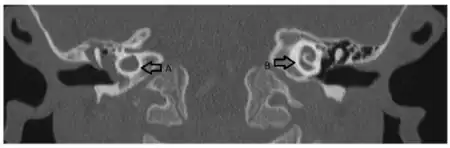

a)Dysmorphic cochlea in right ear (A) and the normal cochlear structure in other ear

This deformity was first described in 1791 by Mondini after examining the inner ear of a deaf boy. The Mondini dysplasia describes a cochlea with incomplete partitioning and a reduced number of turns, an enlarged vestibular aqueduct and a dilated vestibule. A normal cochlea has two and a half turns, a cochlea with Mondini dysplasia has one and a half turns; the basal turns being normally formed with a dilated or cystic apical turn to the cochlear. The hearing loss can deteriorate over time either gradually or in a step-wise fashion, or may be profound from birth.[1]